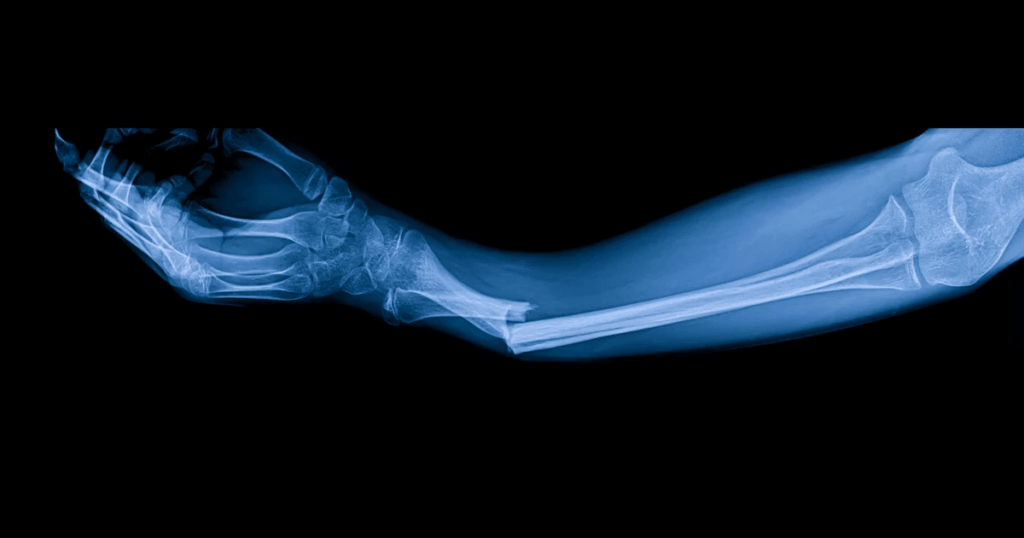

China apresenta ao mundo uma inovação médica que promete mudar para sempre o tratamento de fraturas. Pesquisadores do país desenvolveram uma cola óssea de alta tecnologia que pode reparar ossos quebrados em apenas 3 minutos. O produto elimina a necessidade de cirurgias invasivas, placas metálicas e longos períodos de recuperação, oferecendo uma alternativa menos dolorosa e muito mais eficiente para pacientes de todas as idades.

Os primeiros testes clínicos foram realizados com mais de 150 pessoas que apresentavam diferentes tipos de fraturas. Os resultados mostraram que a cola é segura, eficaz e totalmente bioabsorvível, ou seja, o corpo consegue absorvê-la naturalmente ao longo do tempo. Isso significa que não será necessário remover o material em cirurgias futuras, um dos pontos mais dolorosos e custosos do tratamento tradicional.